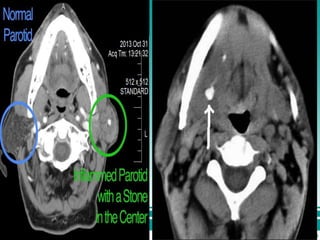

£.Non contrast CT

• Has a 10 fold greater sensitivity than plain

film radiography for detecting calcification

• Technique of choice for detecting small

calculi

£.Non contrast CT •Has a 10 fold greater sensitivity than plain film radiography for detecting calcification • Technique of choice for detecting small calculi